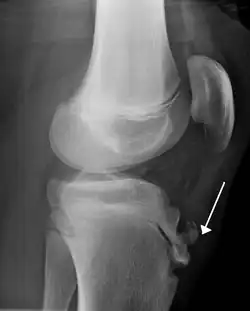

Lateral view X-ray of the knee demonstrating fragmentation of the tibial tubercle with overlying soft tissue swelling.

Risk factors include overuse, especially sports which involve frequent running or jumping.[3] The underlying mechanism is repeated tension on the growth plate of the upper tibia.[3] Diagnosis is typically based on the symptoms.[3] A plain X-ray may be either normal or show fragmentation in the attachment area.[3]